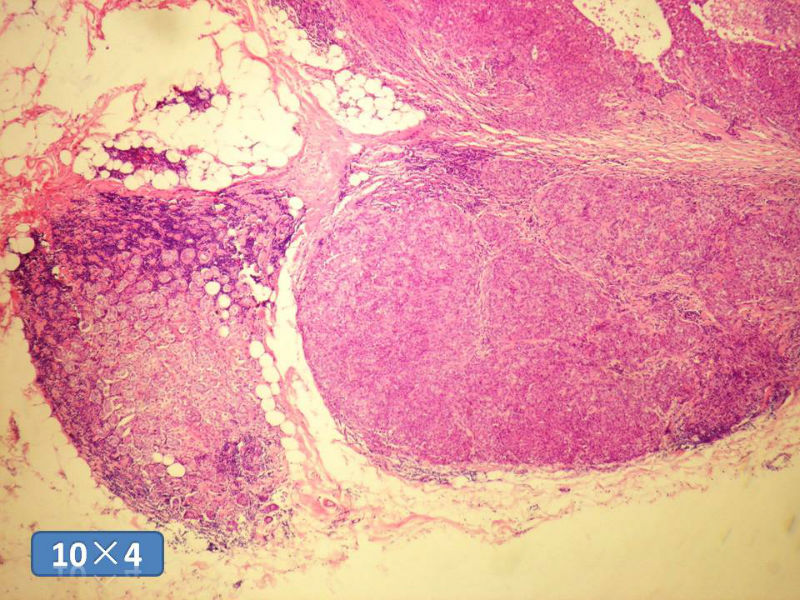

女性,50岁,乳腺肿物,冰冻切片(图1-25)

图1